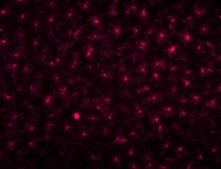

与A公司抗体(兔源单克隆抗体)比较

|

A公司抗体 (兔源单克隆抗体) |

单克隆抗体 (产品编号:018-28523) |

物种:小鼠 部位:大脑皮层 样品:冰冻切片 稀释率:1:1,000 |